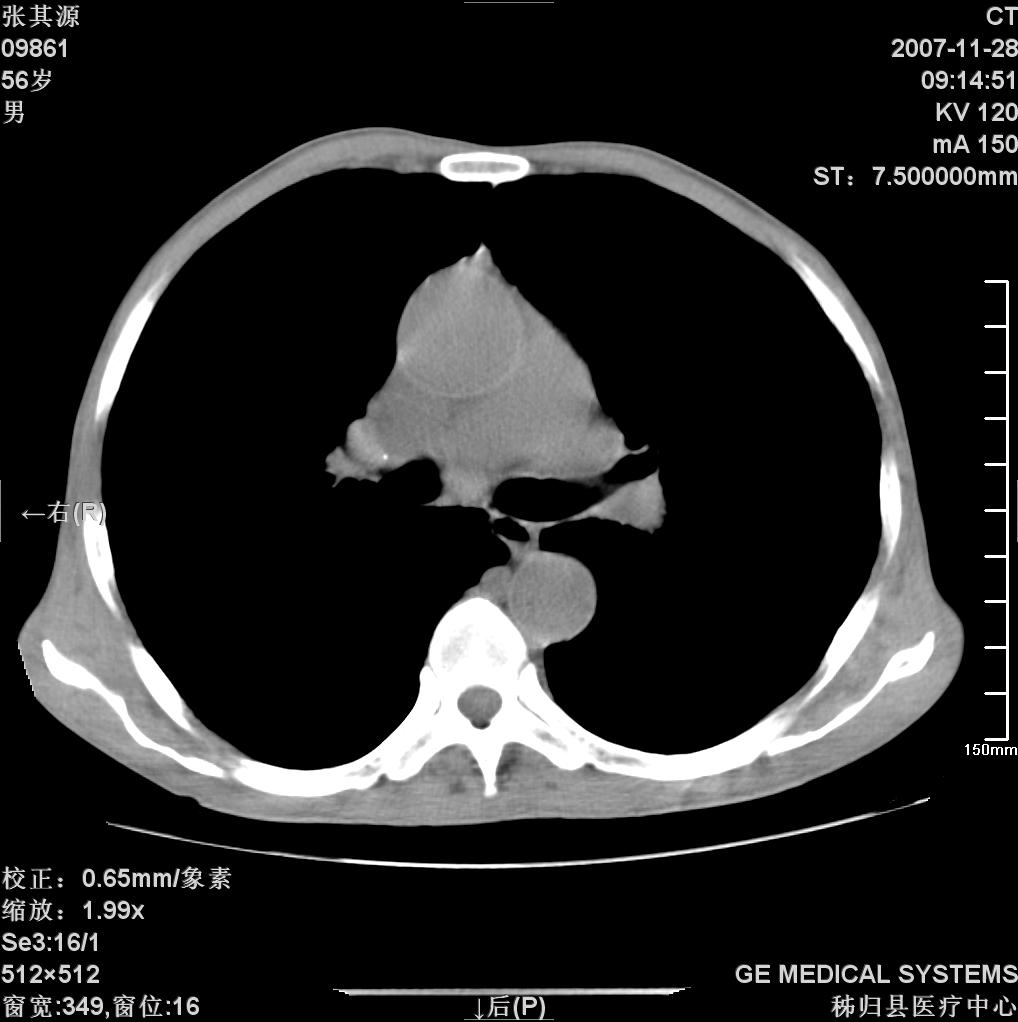

患者因阻塞性黄疸入院,发病前10天持续中等程度发烧.术前检查发现两肺弥漫性病变,请各位大虾会诊,除了考虑急性血源性肺结核外,还有其他什么疾病可能.

补充一下,该患者没有与尘肺相关职业史。请大家帮忙会诊一下,外科医生打算为其做胆总管肿瘤做手术的,现在在等我们的结果。谢谢各位了。

双肺多发粟粒样病灶,右肺胸膜下结节样病灶,气管前腔静脉后及隆突下均见肿大淋巴结,结合胆道肿瘤病史首先考虑转移。另外心影密度略低,时间格显示,是否有贫血?查明白再手术吧!